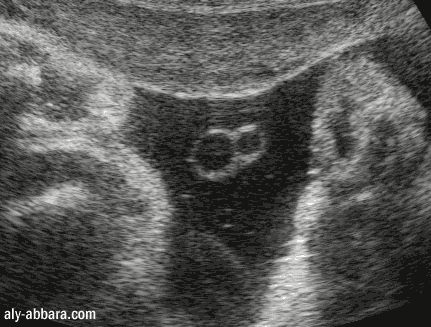

Cordon ombilical fœtal à 38 SA avec

artère ombilicale unique

Il s'agit d'une anomalie isolée chez ce fœtus et sans aucune conséquence à la naissance